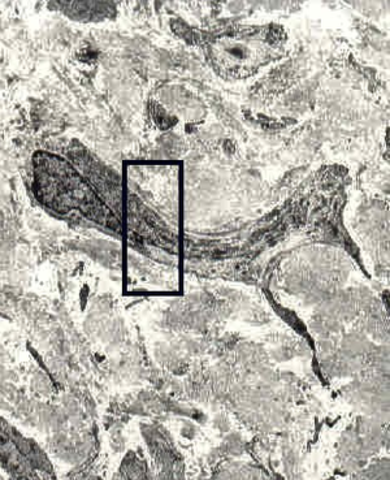

Engrosamiento y Perdida de elasticidad de las paredes arteriales (Ateroma)

El colágeno forma un denso recubrimiento fibroso sobre la placa formando así una placa fibrolipidica

La placa puede ulcerar la pared endotelial a la vez que las LDL tienden a oxidarse y así atraer factores toxicos. (Pro-inflamatorios, y Acimiotacticos)